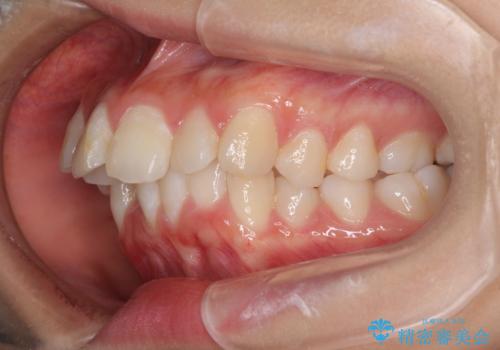

- 出っ歯とデコボコを気にして来院された患者様です。

口元の突出感を改善するため、上下左右第一小臼歯4本の抜歯を行い、ワイヤー装置による矯正治療を行うこととしました。

治療前の上下正中はずれていましたが、骨格的な上下左右差はあまり認められなかったため、正中を揃えて治療を終えることができました。

1年半ほどで治療を終えることができるとは我々も想像しておらず、患者様には大変満足していただきました。